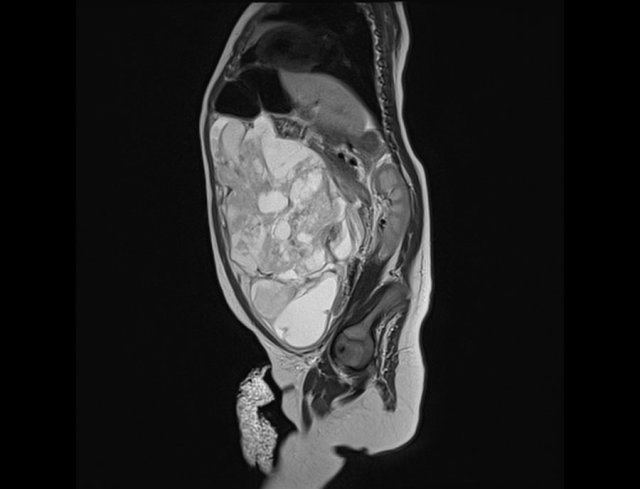

A one-year-old boy presented with a swollen abdomen.

A huge cystic lesion was seen with ultrasound, extending from the liver into the pelvis.

Some debris was visible.

A T2-weigthed coronal MR better shows the extension of the lesion.

At operation it was attached to the ascending colon, which was resected together with the lymphangioma.